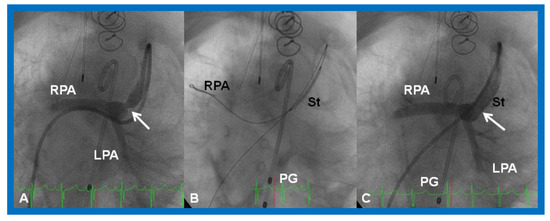

Figure 19.

Selected cine (A) and video (B) frames demonstrating the location of the stent (St) across the atrial septum following St deployment. LA, left atrium; RA, right atrium; PG, pigtail catheter in the descending aorta. Reproduced from Reference [89].